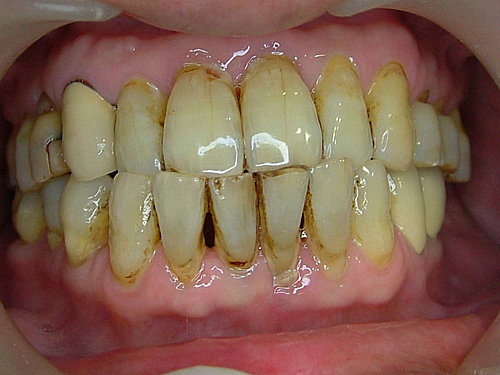

下顎門牙因牙周病 骨頭吸收嚴重 牙齒地基流失 ....

前牙因美觀因素 採即拔即種(immediate implant placement) 植牙後馬上做個臨時假牙(immediate rastoration) 以維持美觀

講話不漏風....

植牙術後看起來的樣子 ..... 不影響日常作息 ....

裝上假牙 大功告成 .... 拜託 !牙齒還是沒刷 看到一層厚厚的牙結石 .... 總不能天天來診所洗牙吧!

唉... 天助 人助 自助.....